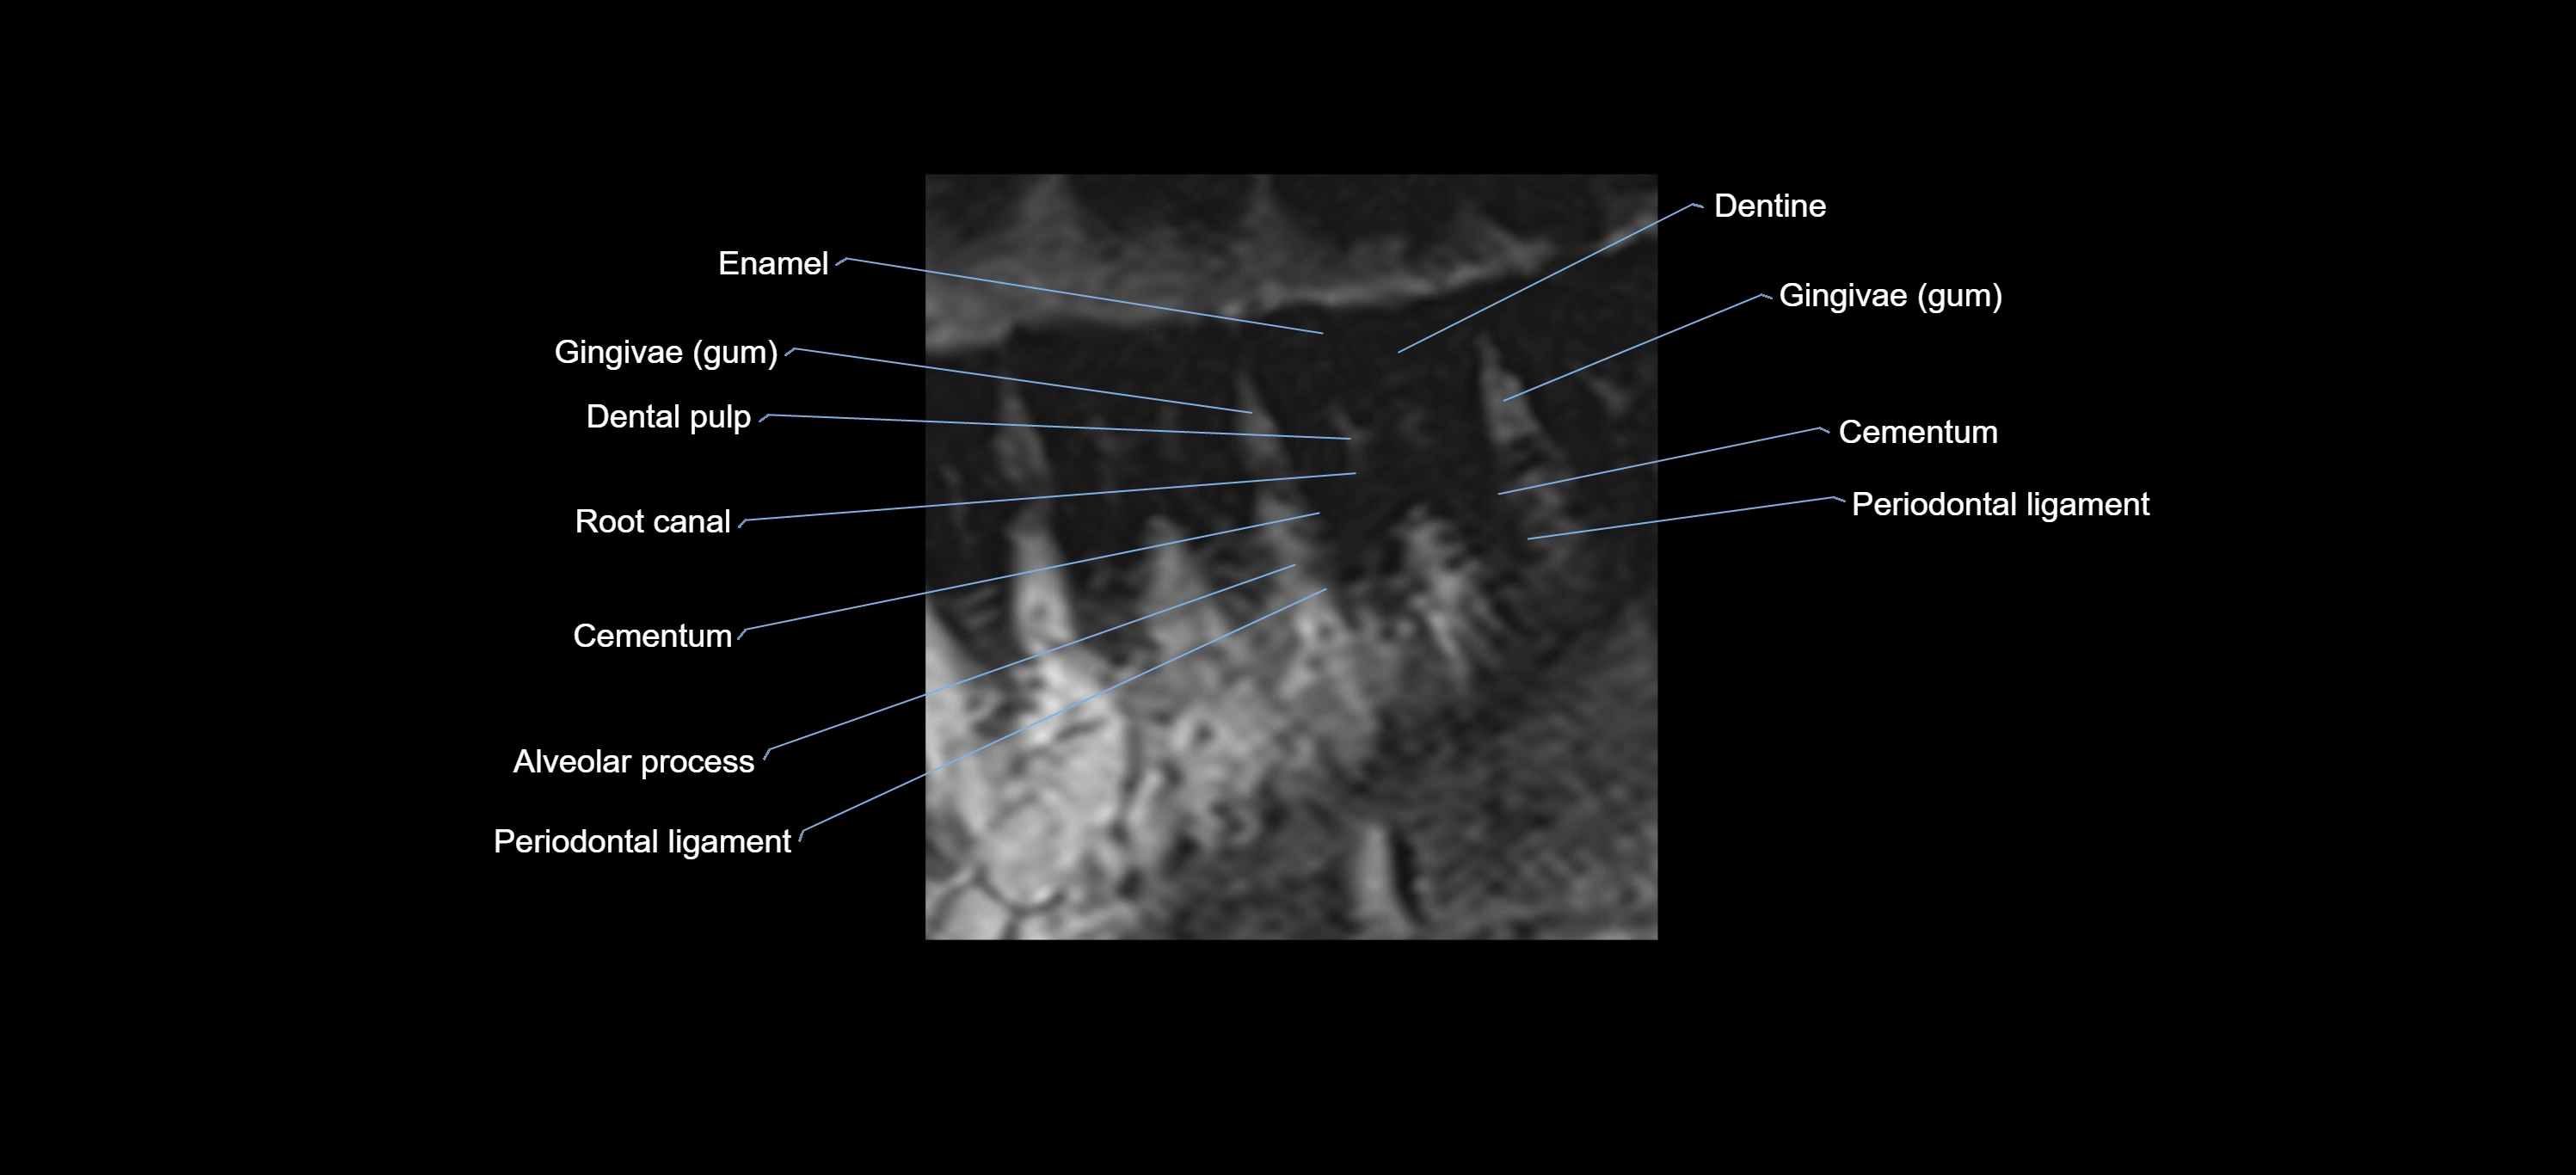

- Cementum

- Dental pulp

- Dentine

- Enamel

- Gum (gingiva)

- Periodontal ligament